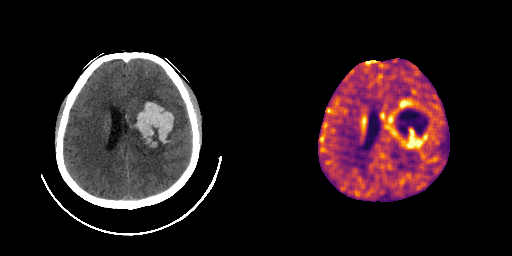

fig:qualitative_ich

ICH

healthy

We show some slices with examples of ICH in \figurereffig:qualitative_ich as well as surface renderings of scans of subjects with cranial fractures in \figurereffig:qualitative_fractures. (As a reference we also included the same examples for the AE in Appendix D in \figurereffig:qualitative_ich_ae.) It is noticeable that the reconstruction error is high where there is an anomaly. The reconstruction error generally seems to continuously depend on the amount of the patch that is anomalous, as the error maps generally seem to be rather smooth.

The performance for the models used for \figurereffig:qualitative_ich and LABEL:fig:qualitative_fractures are shown in \figurereffig:roc_performance. We observe see that the detection of fractures is the more challenging task for our method than the detection of ICH. This might be due to the smaller number of scans available to evaluate it on (see Appendix B). To put these results in context we provided a table with the inter rater agreement on these tasks in Appendix B: The performance in terms of AUROC is around lower than the average raters.